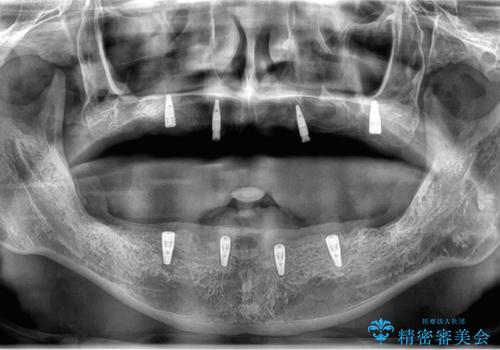

保存できる歯がなかったので全て抜歯をし、インプラントを埋入し、磁性アタッチメントを用いたインプラントオーバーデンチャーで治療を行いました。

- 350万円(インプラント・マグネットアバットメント×8・金属床義歯・骨造成・静脈内鎮静麻酔)費用は治療当時の料金となります